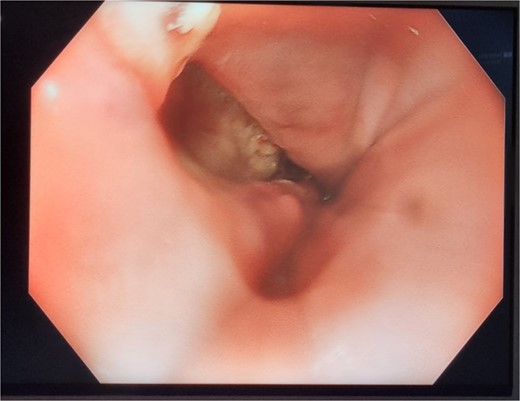

A 89-year-old male, diagnosed with Boerhaave syndrome and oesophageal perforation was transferred from one hospital to another on day 13 post-diagnosis. Initial diagnostic tests, including a gastrografin swallow, identified a defect in the distal left lateral wall of the oesophagus, measuring ˂1 cm with an extraluminal component of at least 5 cm (Fig. 2a).

Patient Two: (a) Before VACStent insertion, showing the oesophageal defect. (b) After VACStent treatment, demonstrating successful defect closure.

On day 14 post-diagnosis, the patient underwent an oesophago-gastro-duodenoscopy (OGD) and VACStent insertion, which was kept in place for 6 days. A CT thorax on day 16 post-diagnosis confirmed proper placement of the VACStent with no ongoing leak (Fig. 2b). The patient underwent ultrasound-guided drainage for a left pleural effusion on day 17 post-diagnosis and remained nil by mouth. Subsequent imaging showed a decrease in the oesophageal defect size, and by day 22 post-diagnosis, the patient was advised to start a soft moist diet, which was well tolerated.